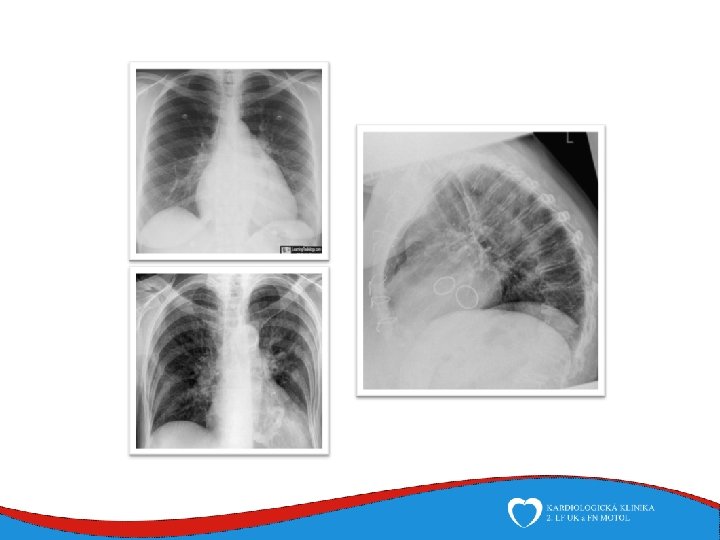

Chest x-ray in valvular disease • Different heart shapes in different valvular heart diseses, ↓specificity, ↓significance • • • Cardiomegaly, pulmonary congestion Widened mediastinum Valve calcifications, prosthetic valves